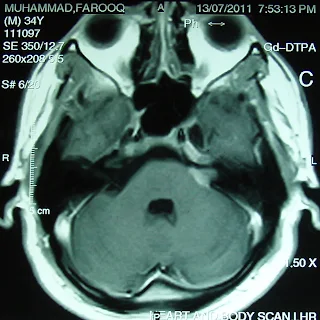

This, 26 years nice man from Karachi had undergone insertion of VP shunt on right side on November 22, 2010 on radio diagnosis of heterogeneous enhancing solid cum cystic mass in posterior fossa in fourth ventricle causing hydrocephalus. This was diagnosed when patient had presented with severe headache on and off associated with vomiting worst since last month and blurred vision since one month.

On referral, he had presented some improvement in headache and vomiting and significant improvement in blurring of vision. Clinical examination had revealed no obvious neurologic deficit. MRI brain spectroscopy had revealed markedly elevated Choline levels up to 399. Patient has referred us for the management with GKSRS. Risk of GKSRS explained all in Urdu along with requirement of strict follow up. These agreed upon wished to proceed. He had treatment with following prescription,